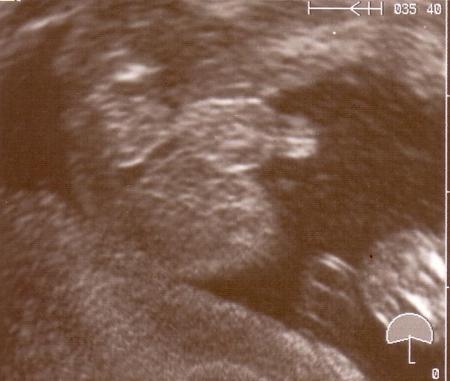

ähm... wenn ich ehrlich bin, dann nach DEM US-Bildchen (von unten auf den Popo) nicht mehr. Zumal uns seit der 16. SSW immer wieder gesagt wurde, dass es ein kleines Kerlchen ist... würde mich dann schon sehr wundern.

...hier noch mal

Bild zu

o.k das ist eindeutig! Aber beim Mädchen soll man wohl nur drei weiße Linien sehen, und ich bin mir da nicht so sicher, obwohl es bei der FD gesagt wurde und bei meiner Ärztin letztens auch noch mal, aber jeder kann sich irren...

also ich habe auch in der 35ssw euíndeutig die hoden gesehen =)